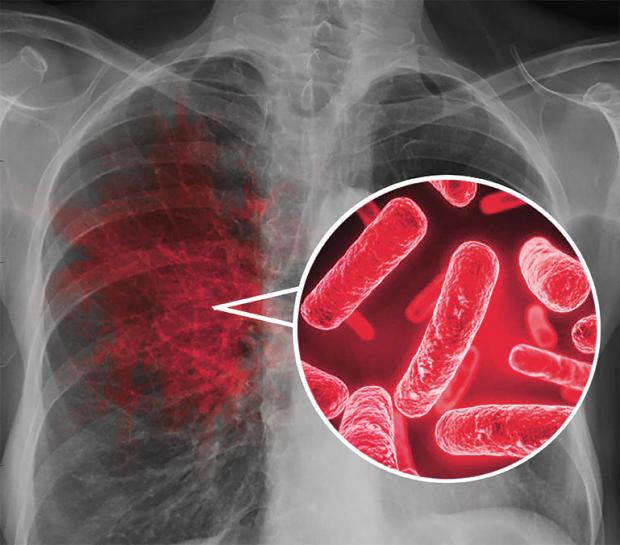

الدرن أو «السل»، أحد أقدم الأمراض المعدية التي عرفها الإنسان، ولا يزال يشكل تحديًا صحيًا كبيرًا حتى يومنا هذا، وينجم هذا المرض عن بكتيريا المتفطرة السلية «Mycobacterium tuberculosis»، التي تستهدف الرئتين بشكل أساسي وتسبب سعالًا دمويًا، وقد تؤثر أيضًا على أجزاء أخرى من الجسم، مثل العظام والجهاز العصبي.

وكشفت أن الأعراض الرئيسية للدرن، تشمل السعال المستمر لأكثر من أسبوعين، فقدان الوزن غير المبرر، التعرق الليلي، والتعب المزمن، مشيرة إلى أن التشخيص يتم عبر اختبارات مثل فحص الجلد، تحليل البلغم، والتصوير بالأشعة السينية.